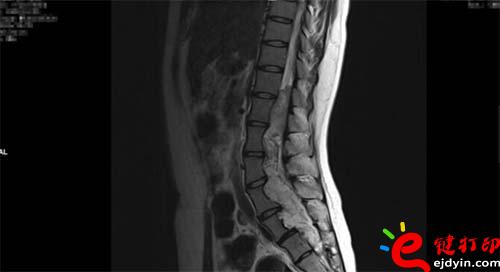

【VR和3D打印在微創(chuàng)椎管內硬膜下先天性腫瘤切除術中的應用】近日,山西省人民醫(yī)院成功完成一例微創(chuàng)通道胸12-骶2椎管內硬膜下先天性腫瘤切除術手術,在手術前醫(yī)院使用了西安鑫威泰科技自主研發(fā)的傲視虛擬現(xiàn)實數(shù)字醫(yī)療系統(tǒng)和3D打印模型進行手術規(guī)劃,制定手術方案,對本次手術的成功起到了至關重要的作用。